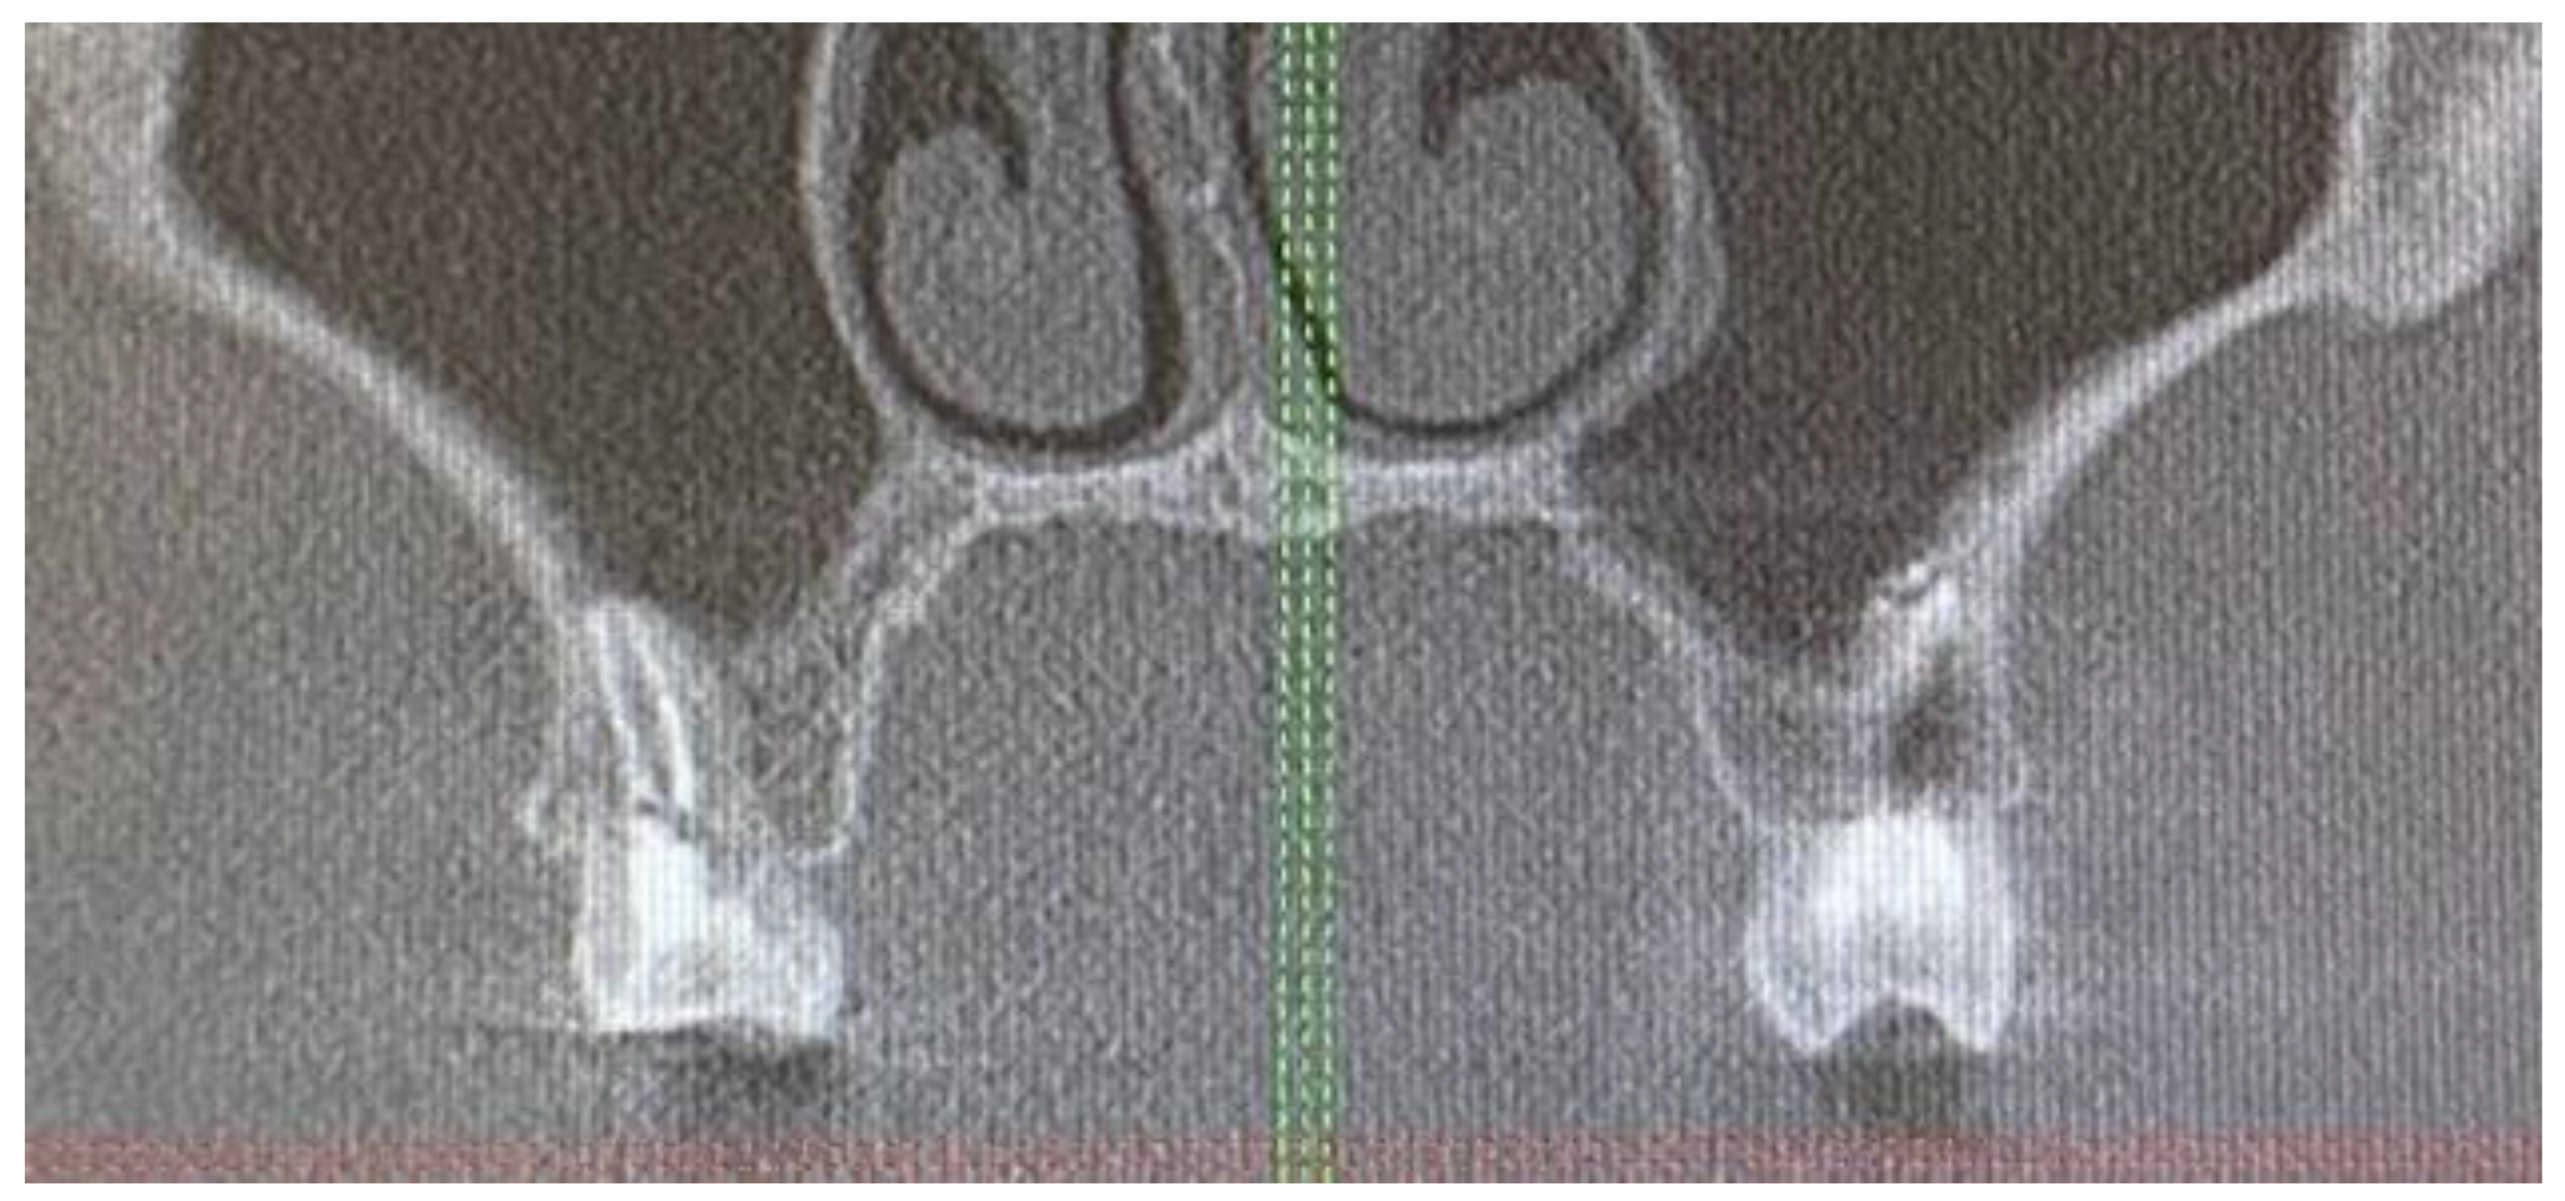

2. Case Description

- A close CBCT evaluation should exclude any odontogenic or teeth-related pathologies, cysts, and tumors in the oral cavity.